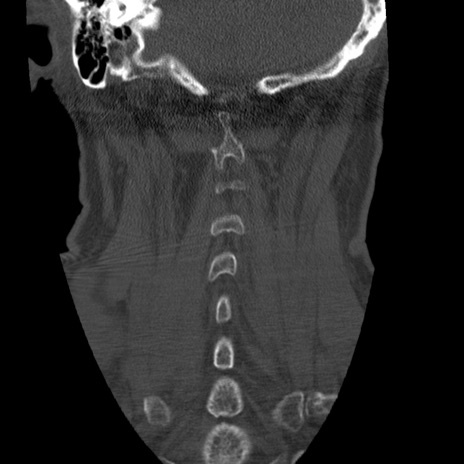

症例50 頚椎CT(冠状断像)

頚椎CT